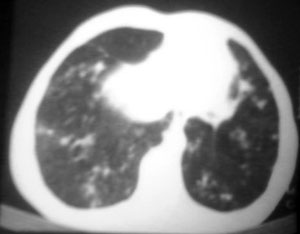

以下是引用逸风在2006-9-12 14:57:00的发言:[br]ct显示双肺上叶点片状及纤维索条状密度不均影,肺野外带近胸膜可见大小不等的含气空腔,壁略厚,境界清晰,未见液平面,中下肺野散在小片状及点状高密度影;纵隔内显示点状钙化,未见明显淋巴结肿大,构成胸廓诸骨未见明显异常.[br]诊断意见:1.双肺结核合并支气管播散;2.双肺上肺大泡.